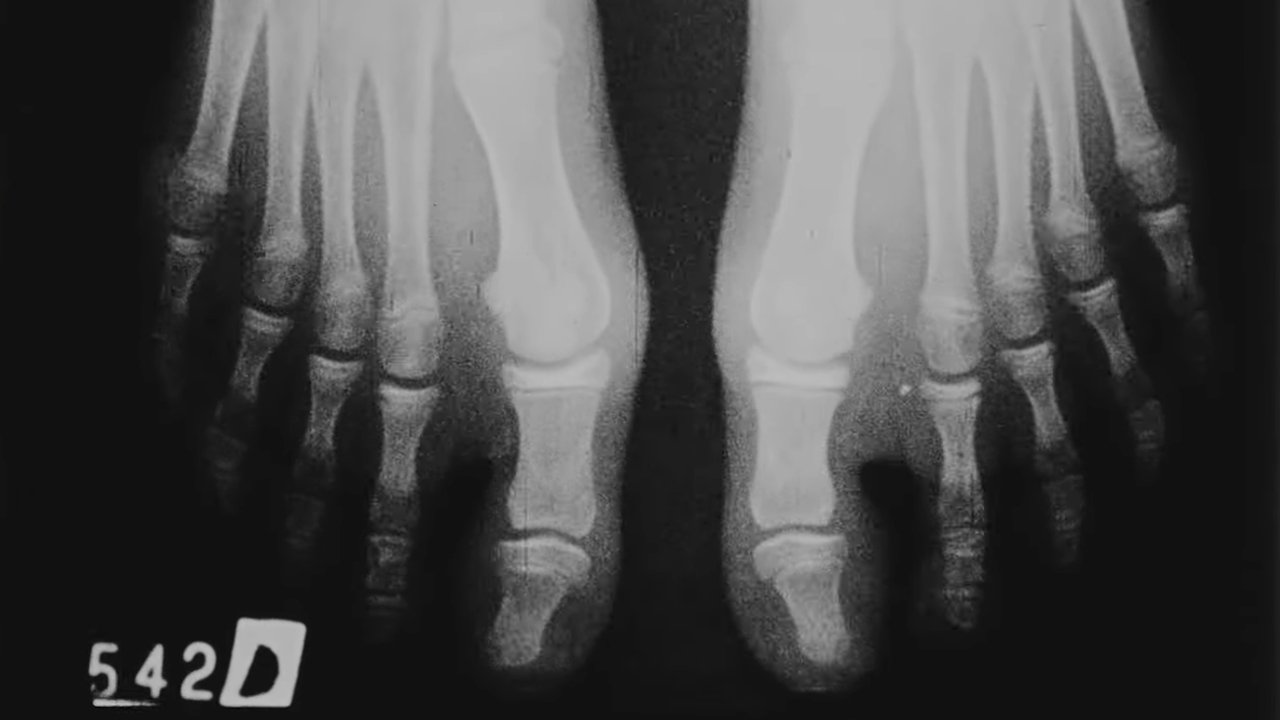

5to. dedo varo

Documentary about a surgical incision to a varus finger.